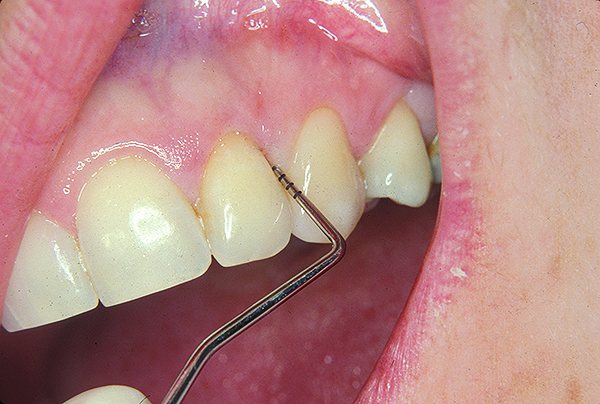

Following active therapy, probing depths of 4 mm or less (Figure 1 and Figure 2) and the absence of bleeding on probing contribute to improved health and stability. Increasing probing depths should alert the therapist to identify etiology and determine whether active periodontal therapy is warranted. The absence of bleeding on probing is a strong predictor of stability, and although the presence of bleeding does not always result in attachment loss, it remains an important parameter to evaluate.14 Bleeding on probing is also an important parameter for assessing implant health during maintenance. Serino et al15 evaluated 27 patients with 19 dental implants over 5 years. Patients were seen every 6 months and they concluded that bleeding on probing was a good predictor for attachment loss and disease progression around the implants (Figure 3).

Fig 3. Bleeding on probing and increasing pocket depths around implant sites indicates a need for treatment.

Figure 3